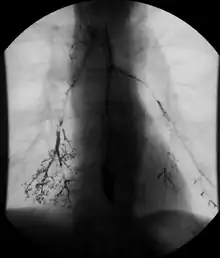

In addition to fasting for 8 hours prior to examination, a laxative may also be necessary for bowel preparation and cleansing.[12] The main aim of this study is to distend the proximal bowel through infusion of large amount of barium suspension. Otherwise, the distension of distal small bowel is generally similar with small bowel follow-through. Therefore, there is a need to pass a tube through the nose into the jejunum (nasojejunal tube) to administer large amount of contrast. This can be unpleasant to the subject, requires more staff, longer procedural time, and higher radiation dose when compared to small bowel follow-through. The indications for enteroclysis are generally similar to small bowel follow-through. Barium suspensions such as diluted E-Z Paque 70% and Baritop 100% can be used. After that, 600 ml of 0.5% methylcellulose is administered after 500 ml of 70% barium suspension is given. Bilbao-Dotter tube and Silk tube can be used to administer barium suspension. The subject should be fasted overnight, any antispasmodic drugs should be stopped one day before the examination, and Tetracaine lozenges can be used 30 minutes before the procedure to numb the throat for nasojejunal tube insertion.[13]

The filling of the small intestines can be viewed continuously using fluoroscopy, or viewed as standard radiographs taken at frequent intervals. The technique is a double-contrast procedure that allows detailed imaging of the entire small intestine. However, the procedure may take 6 hours or longer to complete and is quite uncomfortable to undergo.[23]